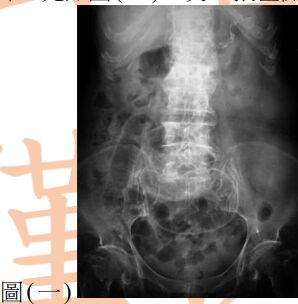

13. 80歲女性為長期糖尿病、高血壓及中風不良於行之病人,因急性腹痛來急診就醫,其平躺之腹部X光如圖(一),另一張左側躺之腹部X光檢查如圖(二),下列敘述何者正確? (A) 推測有腹腔積水,可能為腹腔腫瘤導致 (B) 推測有腹部脹氣,可能為腸阻塞導致 (C) 推測有腹腔積氣,可能為腹腔內中空臟器破裂導致 (D) 為正常腹部影像,只須持續追蹤